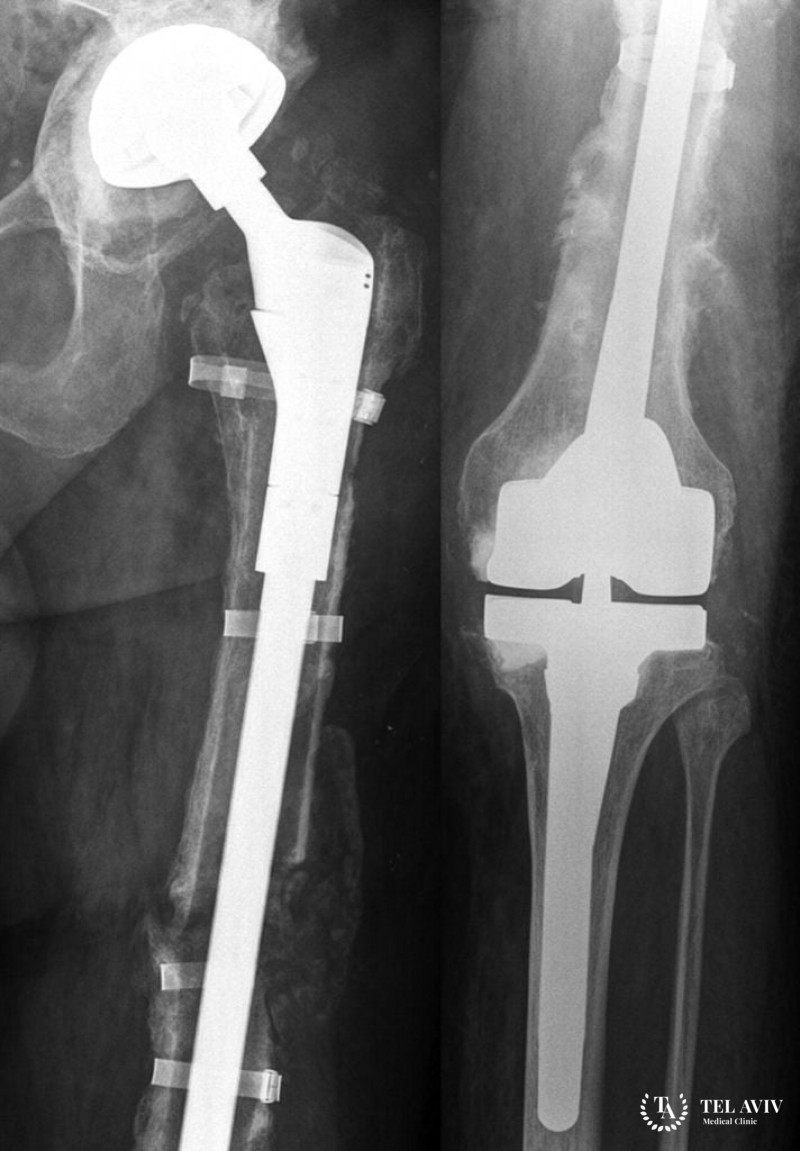

Эндопротезированием суставов называют замену части суставной ткани. В ходе операции имплантируется элементы идентичной анатомической формы. После проведения вмешательства восстанавливается двигательная функция конечности. Современные специалисты проводят комплексные операции по замене локтевых, тазобедренных, коленных, плечевых суставов. При необходимости заменяется часть суставной ткани в пальце. Процедура относится к мелким хирургическим вмешательствам. Она позволяет пациенту избавиться от болей, вернуться к прежней жизни.

Для изготовления эндопротеза используют высокопрочные составы, которые быстро приживаются после установки. Средний эксплуатационный период имланта – от пятнадцати до двадцати лет. После износа необходимо провести операцию по замене протеза. Особенности эндопротезов:

- Конструкции выполнены из нержавеющего стального сплава, металла;

- Специальный цемент плотно фиксирует имплант на костной ткани;

- В составе цемента присутствует хром, кобальт или акриловая смола;

- В эндопротезе присутствует скользящий компонент, если он устанавливается в бедренную или плечевую кость. Он производится из титановых сплавов;

- При формировании поверхности скольжения используют сверхпрочные полиэтилены. Иногда их заменяют алюмооксидной керамикой.